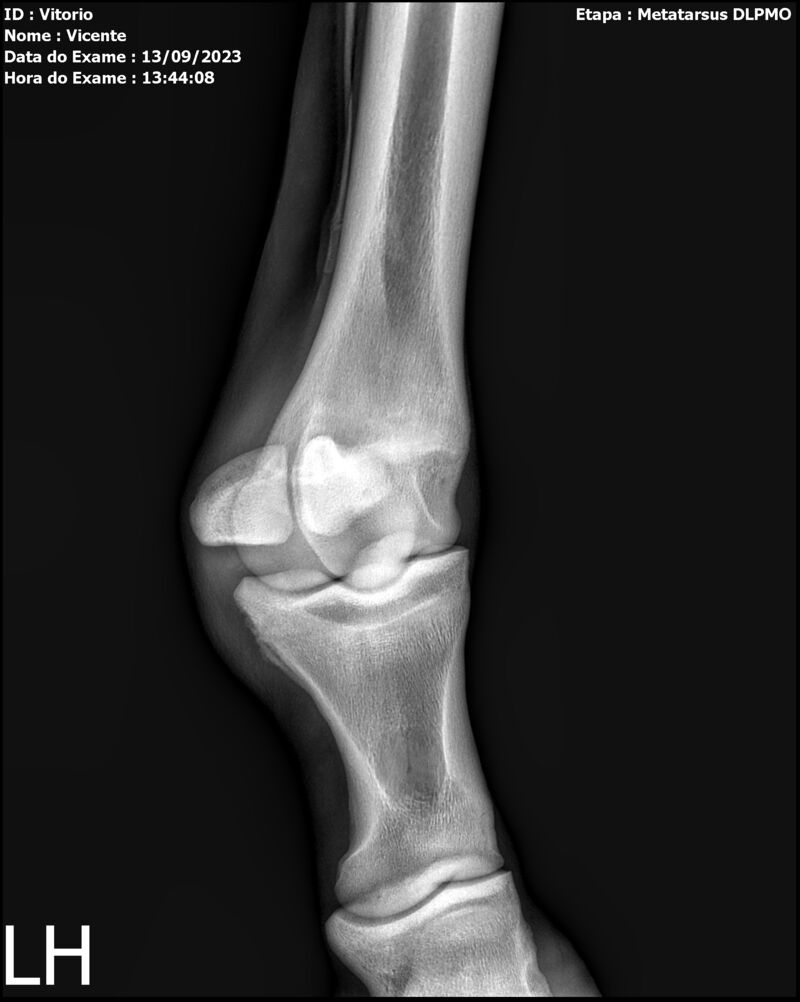

THUNDER ZC

Raça: BRASILEIRO DE HIPISMO

Sexo: MACHO - POTRO

Nascimento: 17/09/2022

Altura Aproximada: 1,54

Pel.: CASTANHO

Registro: EM AND

Vend.: VICENTE CONTE

Local : PORTO FELIZ/SP